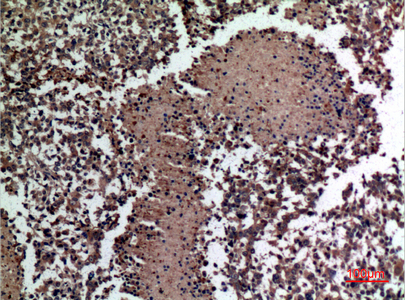

Immunohistochemistry analysis of paraffin-embedded Human lungcancer using HspBAP1 antibody. High-pressure and temperature Sodium Citrate pH 6.0 was used for antigen retrieval. |